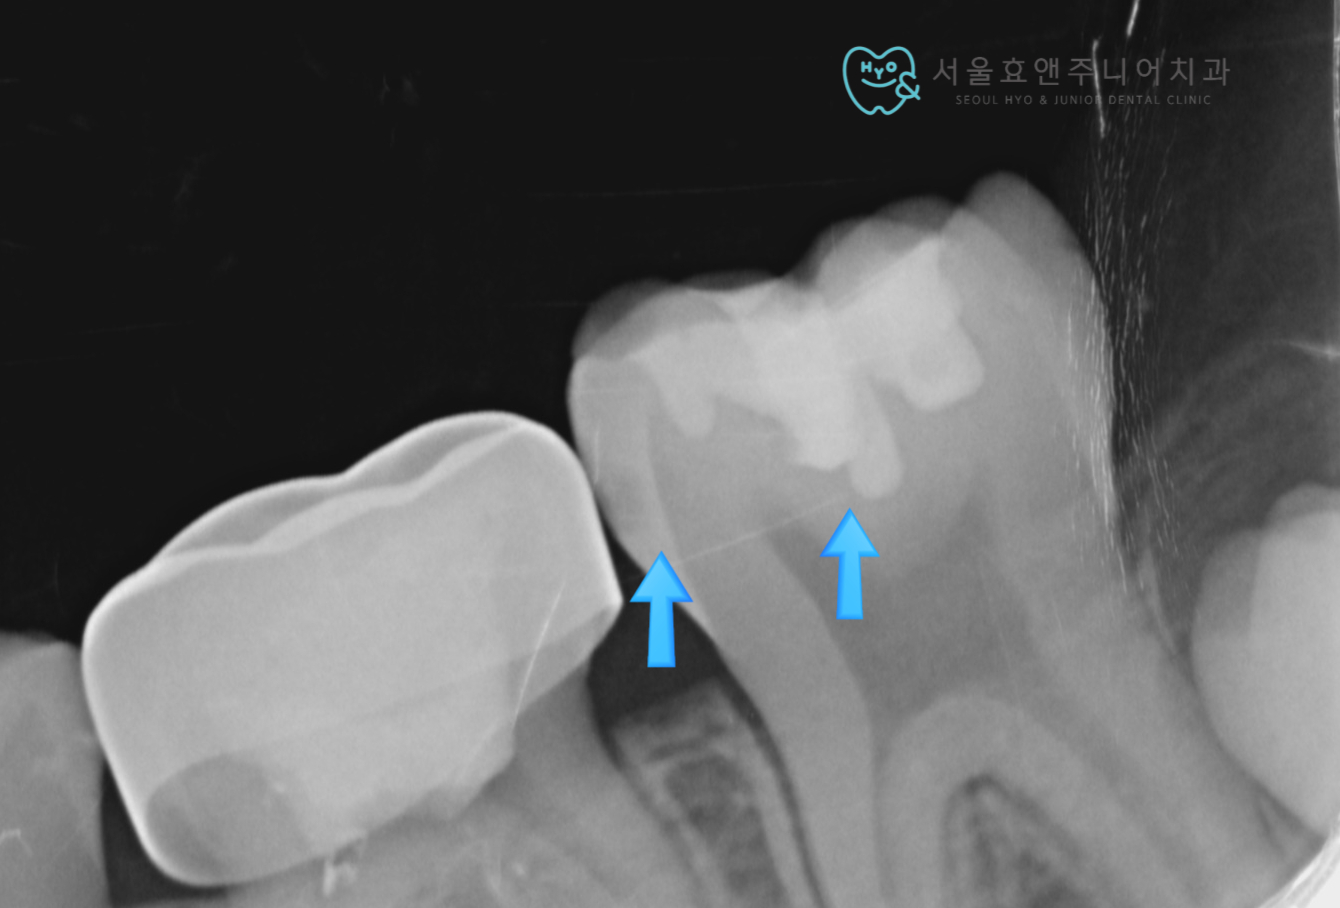

치료 전 사진입니다. 치아의 옆면에 충치가 있고 그 앞으로는 탈락시기가 다가온 유치가 남아있습니다. 이 유치는 이제 빼주면 됩니다. 영구치의 씹는 면에는 타치과에서 오래전 때운 수복물이 있는데 그 아래로도 충치가 거뭇하게 보이네요.

기존 수복물을 제거하고 옆구리 충치도 어느정도 제거했더니 충치가 보입니다. 모두 제거하자 신경이 너무 가까워 집니다. 아직 뿌리가 다 자라지 않은 미성숙 영구치이므로 최대한 신경노출이 되지 않도록 조심스럽게 충치를 제거하였습니다.

가장 깊은 부분, 신경과 가까운 부분에 신경보호약제( MTA) 를 도포하고 사이충치로 인해 벽이 없어진 부분은 단단한 레진을 깔아 벽을 만들어 주었습니다. 레진을 마무리한 후, 옆의 수명을 다한 유치는 발치하였습니다.

치료 4개월 뒤 사진입니다. 정말 깊은 충치였고, 벽이 없어진 사이충치였는데도 인레이없이 보험레진만으로도 증상없이, 이차충치 없이, 치아가 잘 기능하고 있습니다. 앞으로도 정기검진 예정입니다.